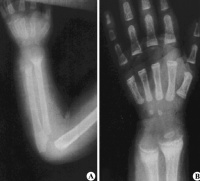

佝偻病骨骼x线表现

生化改变轻微,骨骼X线摄片可无异常

①X线:钙化带模糊,干骺端增宽,边缘呈毛刷状或杯口状改变。

(2)理化检查:X线临时钙化带重现;生化恢复正常。